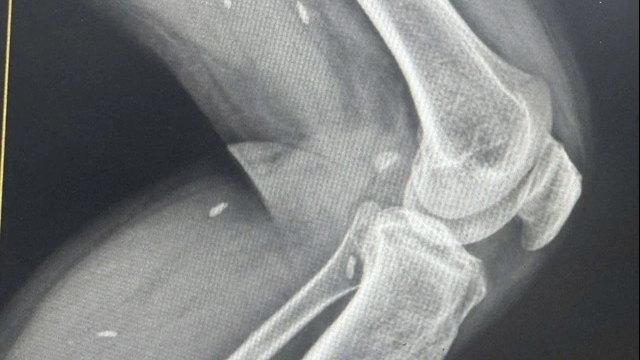

Thạc sĩ. Nguyễn Thị Bích Hải, Phó Trưởng phòng Kế hoạch - Điều dưỡng, cùng các y bác sĩ đại diện nhiều khoa phòng và bệnh nhân đang điều trị tại Khoa Hồi sức Cấp cứu, khoa Ngoại, khoa CSSKSS-Phụ sản nhấn mạnh tầm quan trọng của việc duy trì đối thoại hai chiều giữa nhân viên y tế và bệnh nhân, coi đây là cơ hội để lắng nghe, thấu hiểu và không ngừng hoàn thiện chất lượng chăm sóc.